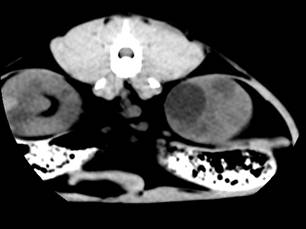

Даний факт знаходить підтримку у роботах

сучасних дослідників гуманної медицини в цій галузі. Досліджуючи цю тварину

через 14 днів, ми відзначили зниження інтенсивності сигналу вищевказаного

кістозного утворення (рис.).

Поясненням цього може бути поступовий розпад гемоглобіну, що зменшує

інтенсивність сигналу. Це припущення також висувається у гуманній медицині. В

той же час, інтенсивність деяких кістозних утворень залишалась постійно

високою, що може вказувати на інфікування вмісту кісти та зумовлене наявністю

великої кількості білка у кістозній рідині. Така тенденція знаходить

відображення у деяких публікаціях.

Рис.7. КТ

нирок кота. Полікистоз в стадії компенсації: а-неускладнена кіста; б -

геморагічна кіста

Рис. 8. КТ

кота. Полікистоз нирок у стадії субкомпенсації. Деформація

миски

правої

нирки.

Зменшення

інтенсивності

сигналу

геморагічної

кісти

(а)

Ниркова миска візуалізувалась у всіх

випадках у вигляді вузької гіподенсної щілини, контури якої залежали від

ступеня гідронефротичних та кістозних змін органа (рис.).